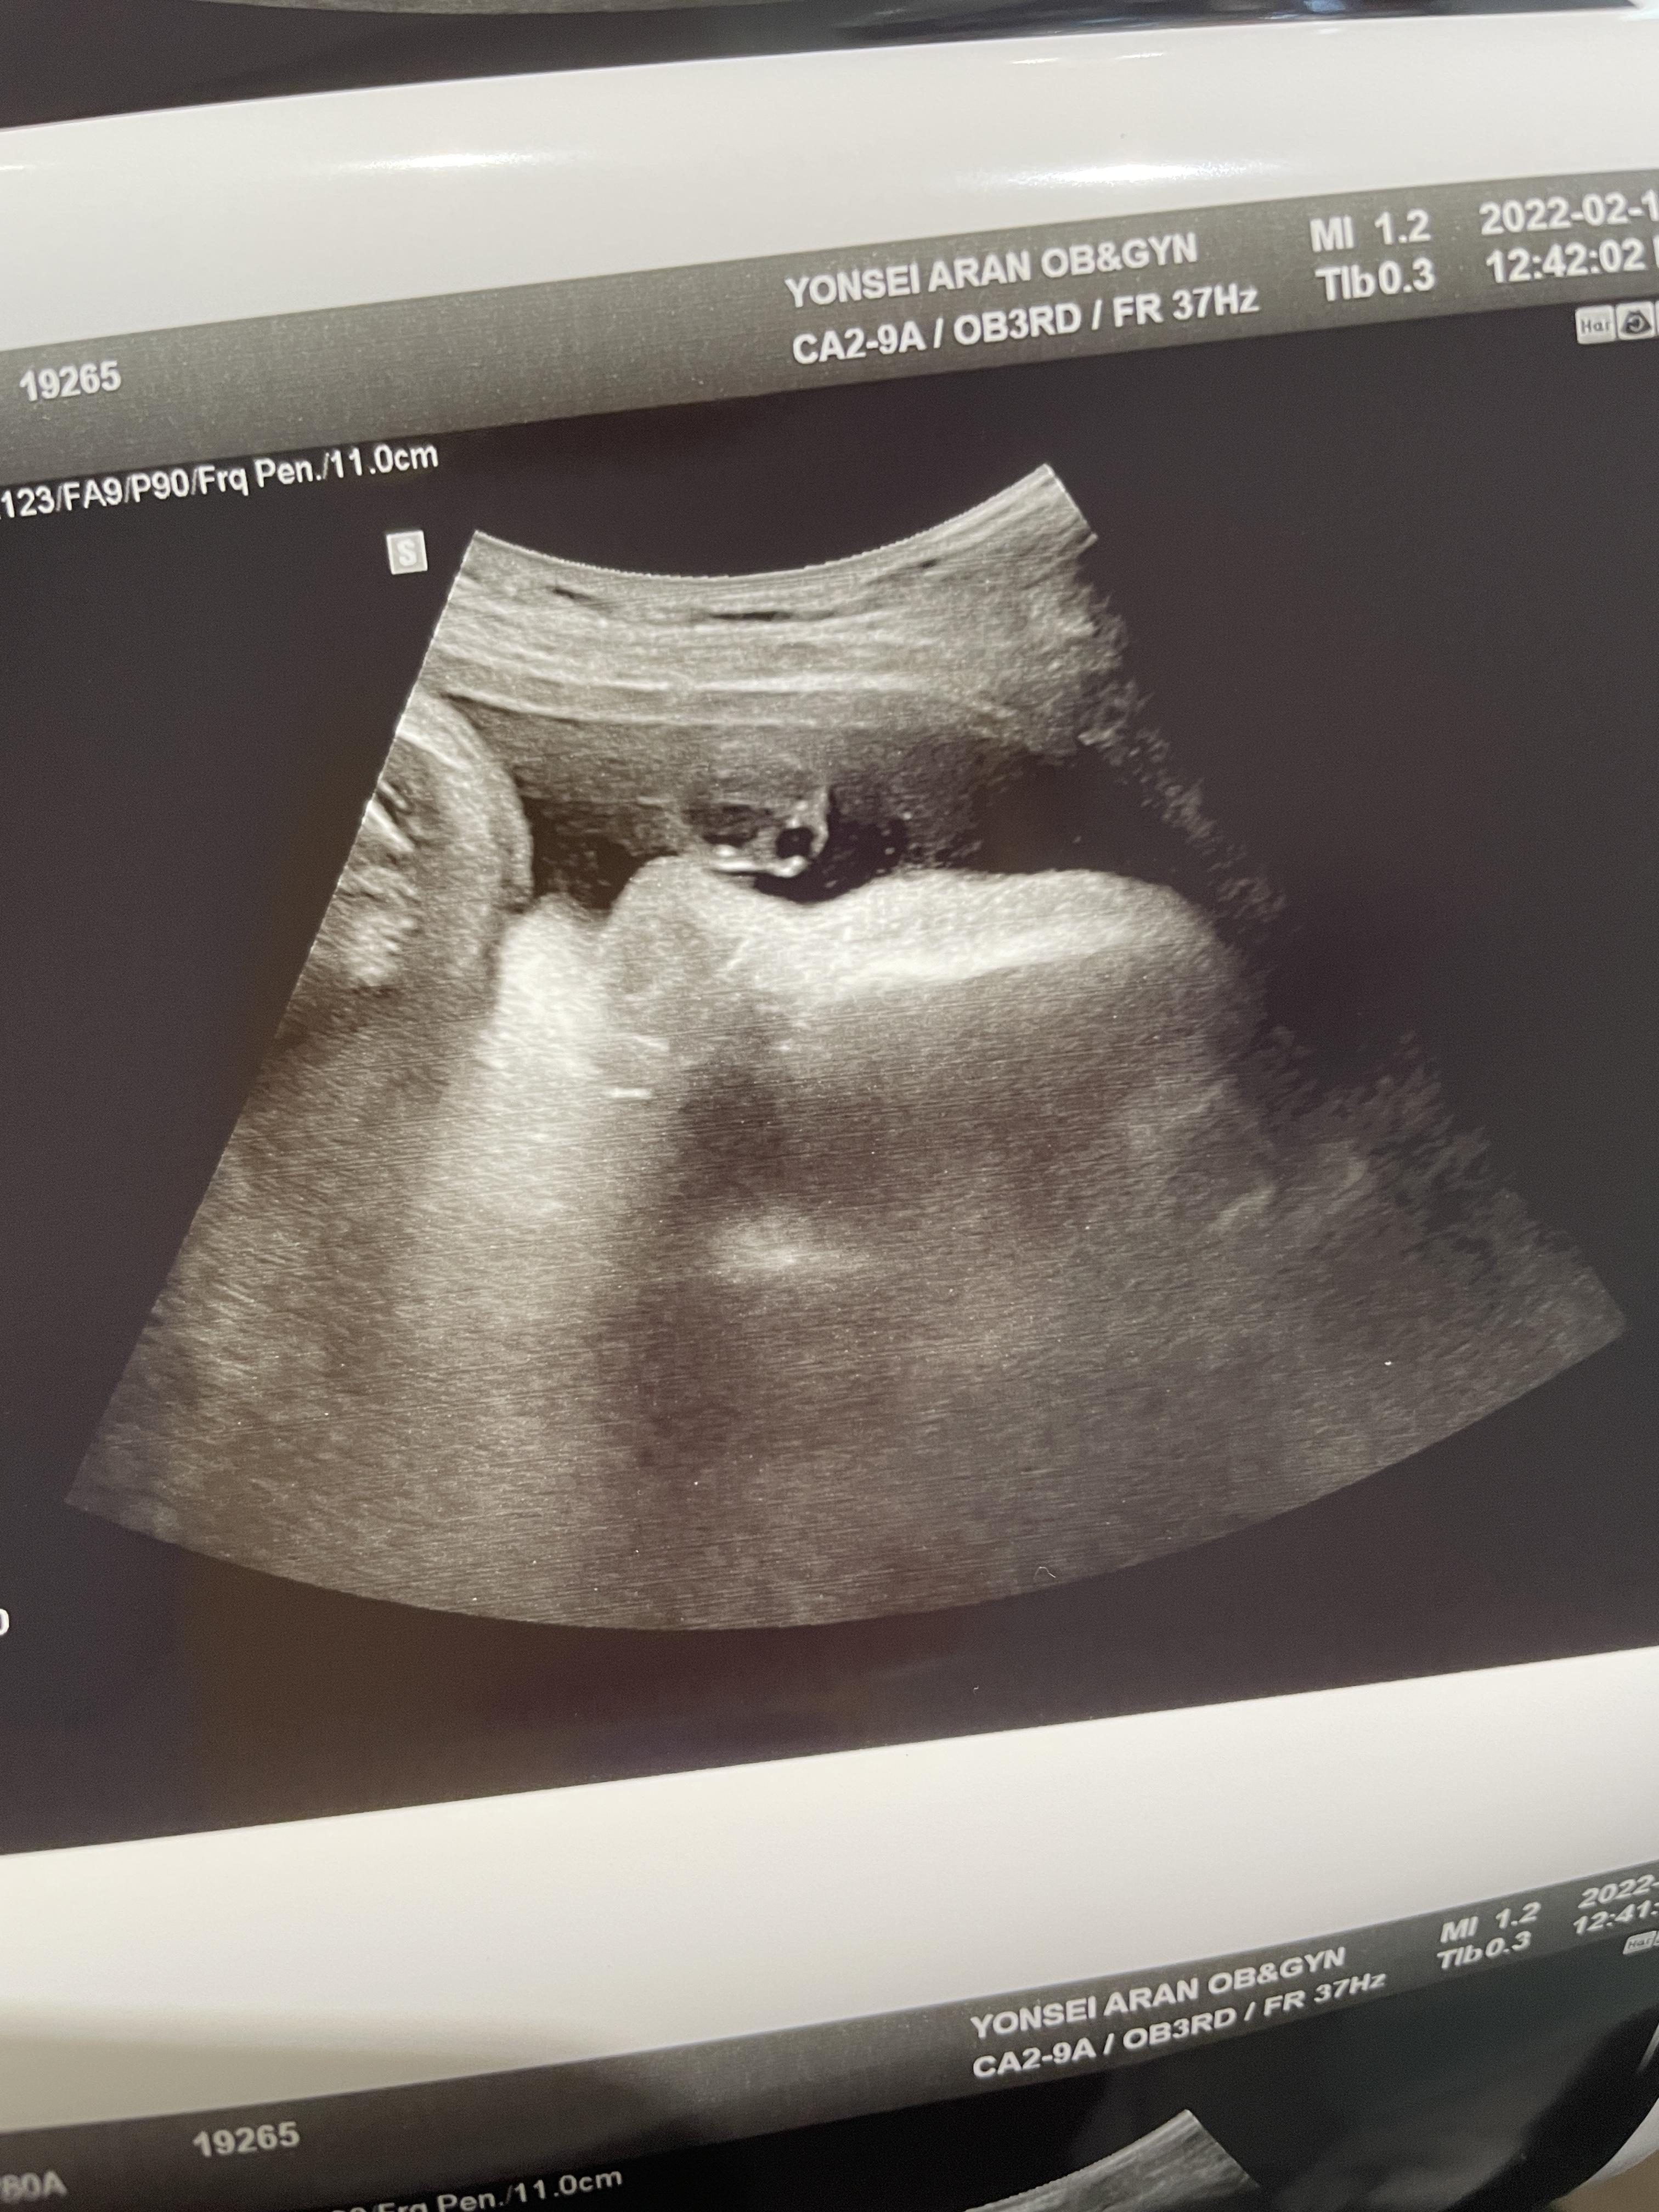

38주 1일차 진료

애기가 얼굴이 너무 잘보인다며 웃으셨다.

하나도 안내려왔다고...ㅠ

그와중에 머리는 역시 커졌고,